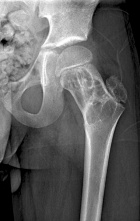

S.P. - 12 year old male with left hip pain after a minor fall

Zoom image: Radiological image Radiological image.